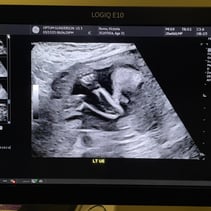

Greetings! I’ve been away from my updates for a couple of weeks, so lets get you caught up on all the things! First off, we had our Anatomy Scan today and hit the half way mark of the pregnancy. WOW. Our baby girl is doing so so well. From head to toe, she’s about 9-10inches and weighs 12oz. A week or two ago I stopped having all pregnancy symptoms besides the obvious physical changes. This was awesome but also made me a little uneasy. I also have not felt much movement and waiting 4 weeks for my 20 week appointment was starting to make me very antsy in a horribly, anxious way. Having a miscarriage the first time around has really made it difficult to relax and feel confident that everything is going well. Last week Steven went ahead and bought me a Doppler to listen to our baby’s heart beat at home while we waited for our next appointment. Once it came in and I found that wonderful sound of her heart, whew! Instant relief. Today was even better! Not only is SHE healthy, but so am I! I started going to the gym a few days out of the week and signed myself up for a 4 week Prenatal Yoga class that takes place every Saturday. My blood pressure today was 118/72 and weighing 129 which is 4 pounds more than my last appointment. I feel wonderful and even more excited than I was before to meet our girl! We’ve started clearing out the room that will be her nursery and are so grateful to the friends and family that have already started pouring their love into us and our baby with the registry gifts! Steven also surprised me with setting me up to visit family in Texas next month during my Spring Break from work. What a guy. 💕 I hope you all enjoy these photos! You‘ll see her profile with her cute little nose! There’s one of her foot, one of her crunched up with her legs bent, a crazy one of her that looks like a Halloween photo, and it’s hard to tell but one of her lips and nose. She was spinning and drinking and kissing us while she was having her first photoshoot. I will start feeling her more in the next couple of months. I have an anterior placenta so it makes things a little harder to feel since its placed in the front of my uterus. She is having fun, nonetheless. That’s all for now! We love you aaalllllll. A note from Steven: we could clearly tell during the sonogram that she gets her dance moves from her daddy.